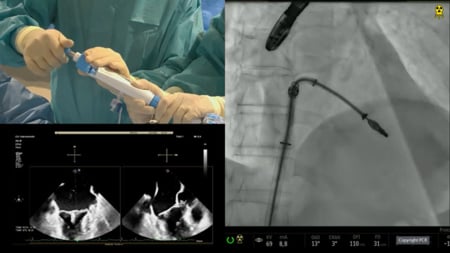

This session presents a comprehensive overview of innovative interventions addressing complex structural heart conditions, including tricuspid and mitral valve diseases. Highlights include clinical experiences from the PESCAMI registry on mitral indirect annuloplasty, advanced percutaneous procedures for large pulmonary arteriovenous malformations, and transcatheter bicaval valve implantation for severe tricuspid regurgitation. Additionally, it covers unique cases such as endovascular closure of post-oesophagectomy aorto-conduit fistula and management of torrential tricuspid regurgitation in rheumatic multivalvular disease.

• Transcatheter bicaval valve implantation for symptomatic severe tricuspid regurgitation in right heart failure